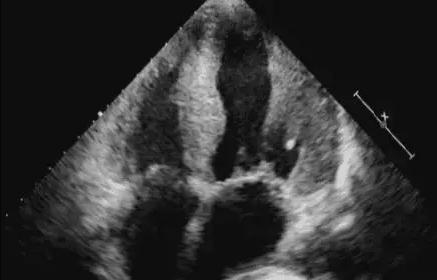

心悸亢進の主な病理学的変化は心室壁の肥厚である:

1.左室腔の拡大を伴わない心室間中隔および左室壁の一様な求心性肥厚;このタイプが最も一般的である;

2、左心腔が拡大し、心室壁の肥厚は目立たず、偏心性肥大を示し、このタイプはほとんどが左心不全を伴う;

3.左心室後壁の不均一な肥厚を伴う心室間隔の著明な肥厚は、肥大型心筋症と区別すべきである。

超音波診断のポイント

2.心室間隔および左室壁の均一な肥厚;

3.左心拡大;

4.左室壁運動の振幅の減少;

5.相対的僧帽弁閉鎖不全症。